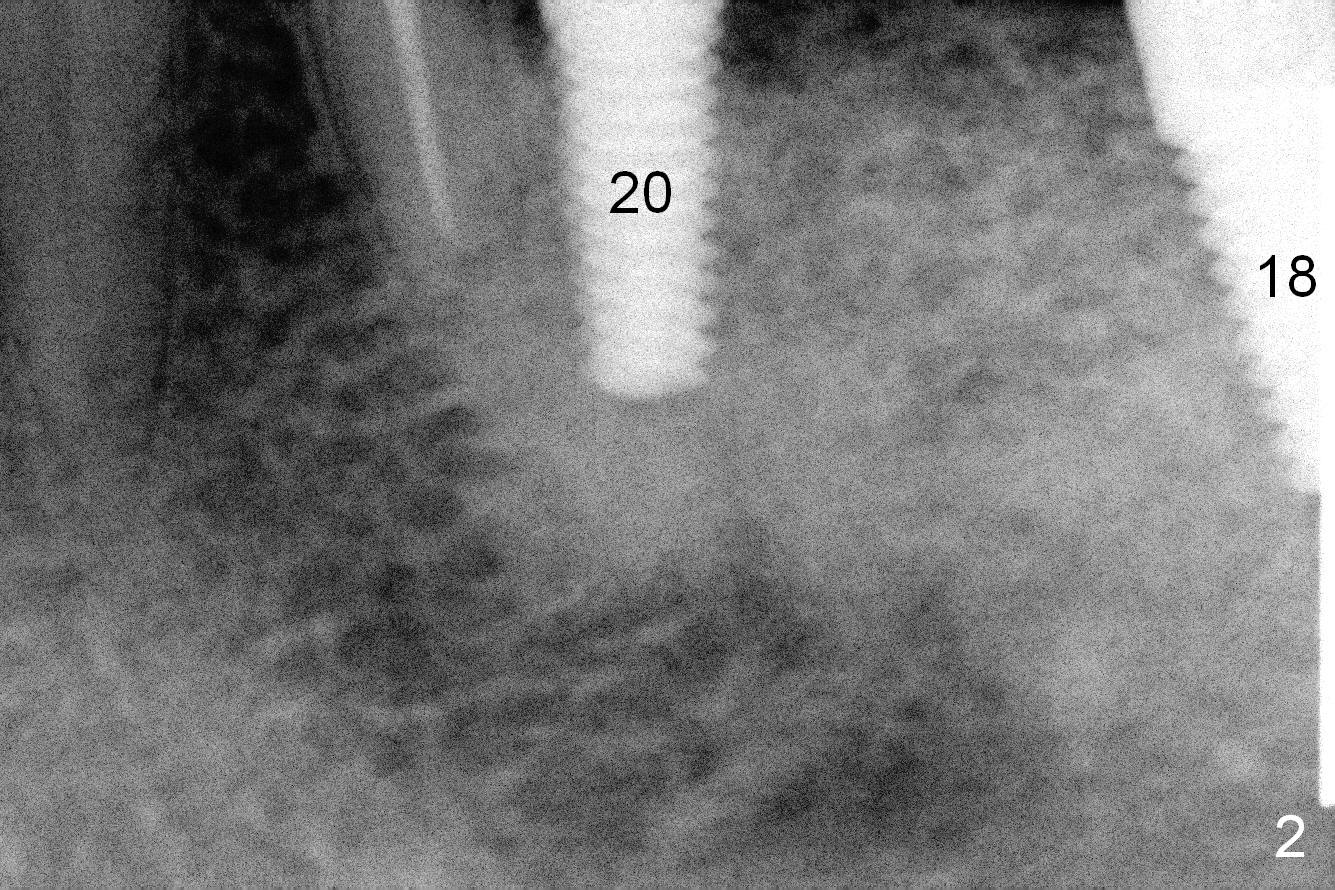

The sites of osteotomies at #18 and 20 are decided by the surgical stent (Fig.1). A 4x14 mm implant is placed at the site of #20 (Fig.2), and a 5x14 mm one at #18 (Fig.3) with primary stability. When 3 mm long abutments are placed for an immediate provisional (Fig.4 A), there is no or limited clearance with the opposing dentition (Fig.5). In spite of the fact that the implants are placed deeper, the abutments and the opposing supraerupted teeth #13 and 15 (Fig.5 arrows) have to be reduced. Finally the abutment at #18 has to be removed. No provisional is fabricated. Periodontal dressing is applied around the abutment at #20 and the adjacent teeth. It appears that the tissue-level implant is not suitable for the 2nd molar with limited vertical clearance.